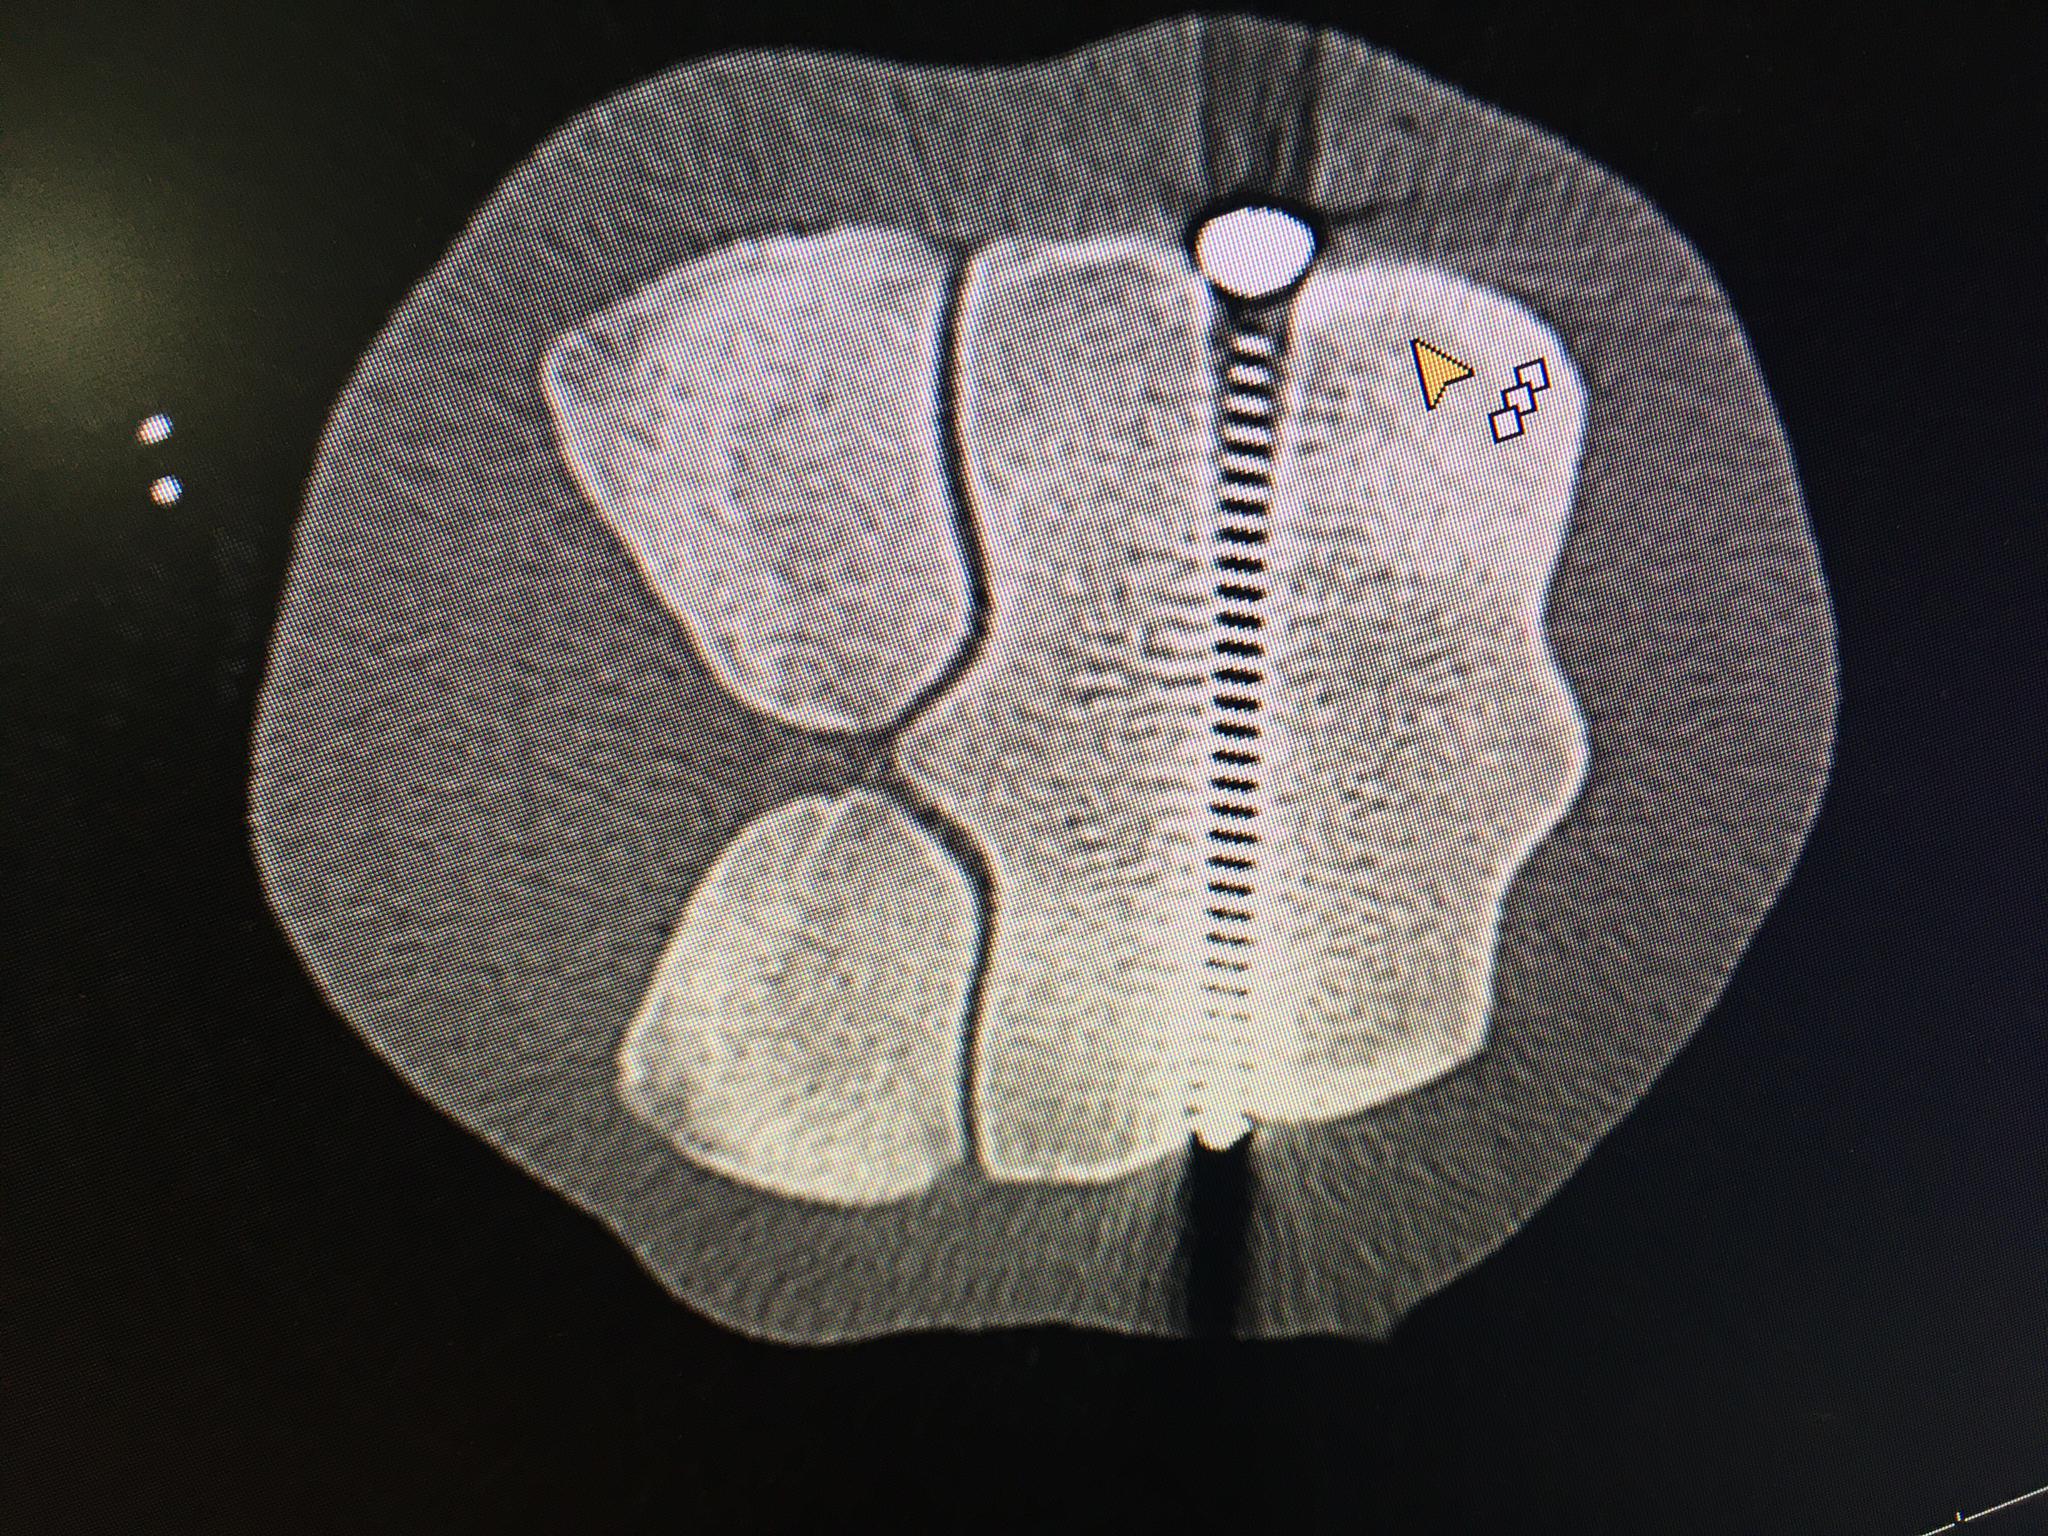

Ein postoperatives Bild, auf welchem die Schraube zu sehen ist, welche den Knochen stabilisiert.

...und von anderem Winkel aufgenommen.